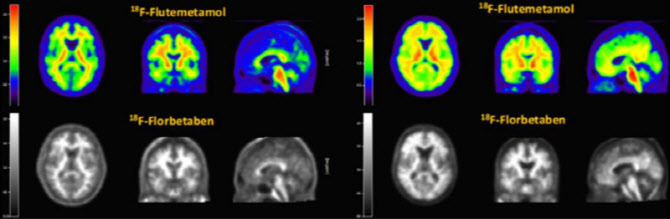

| | 알츠하이머 치매 진단을 위해 쓰이는 '비자밀'(윗쪽 컬러 사진)과 '뉴라체크'(아랫쪽 흑백 사진) PET-CT 영상 비교 (자료=듀켐바이오) |